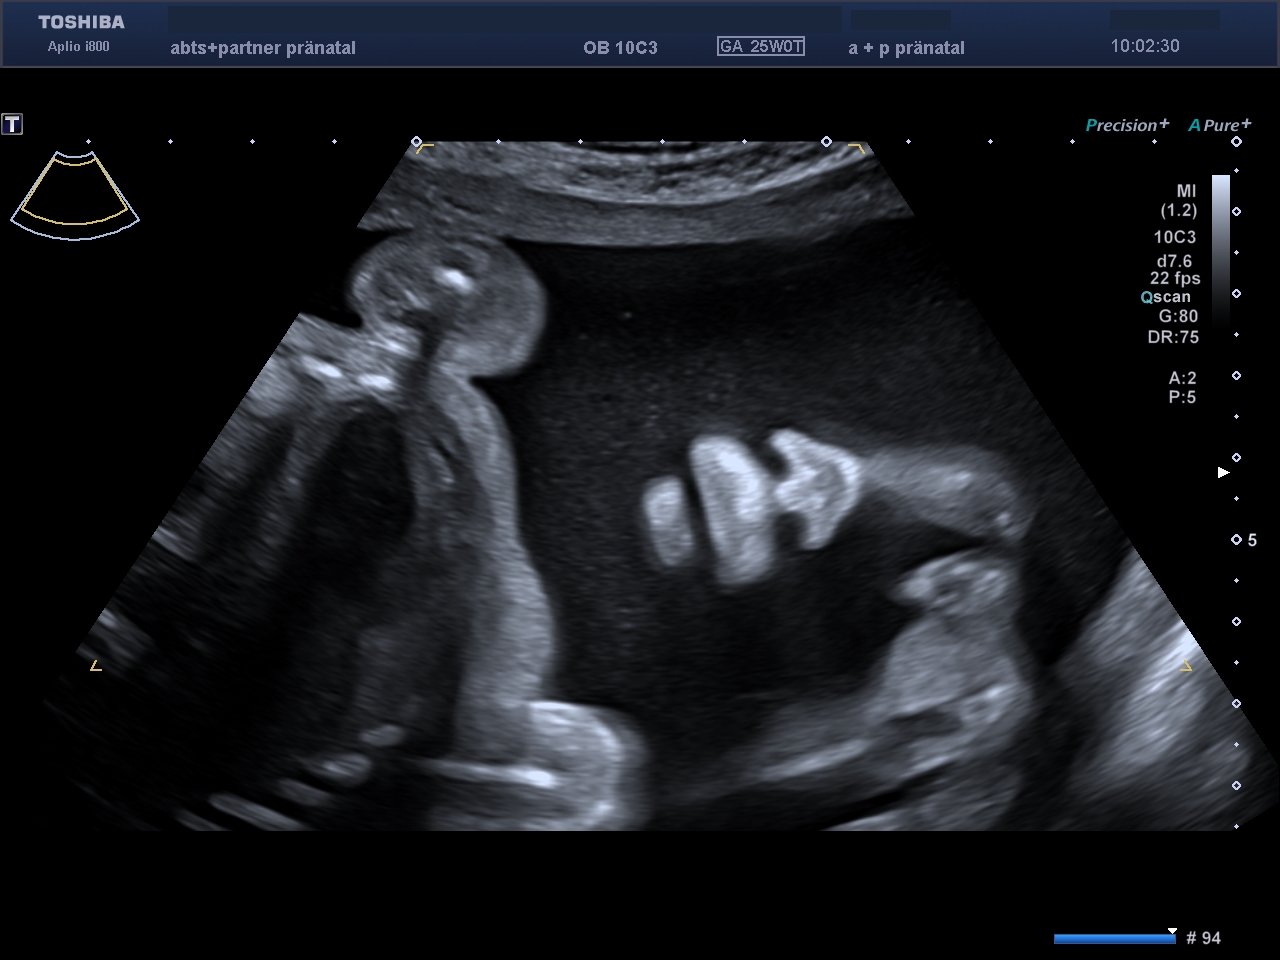

Das Baby in der Übersicht. So können Wachstum und Proportionen, Herzschlag und Gesicht gesehen werden.

Auch Arme und Beine mit Händen und Füßen lassen sich bereits untersuchen.

Bei besonders guten Untersuchungsbedingungen können auch 3D/4D-Aufnahmen entstehen.